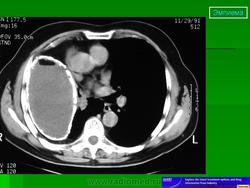

Лучевая диагностика. Рентгенологическое обследование в диагностике плеврального синдрома занимает ведущее место. Рентгенологическая картина свободного выпота, когда объем жидкости увеличивается, характеризуется затемнением наружного костно-диафрагмального синуса, части легочного поля над куполом диафрагмы с косой верхней границей тени, что и позволяет предполагать наличие плевральной жидкости уже по обзорной рентгенограмме. Важным элементом обследования является определение признаков свободного растекания жидкости в плевральной полости, для чего применяется латерография. Латерограммы, выполненные одновременно на вдохе и выдохе, позволяют судить о количестве свободно перемещающейся жидкости. Как известно, при туберкулезном плеврите экссудат довольно быстро может подвергаться организации (фибринизации), отграничению или осумкованию. При средних и больших объемах выпота выявить эти признаки возможно лишь при латерографии на больном и здоровом боку, а также при УЗИ и КТ, что полностью подтверждено при сопоставлении этих картин при визуальном торакоскопическом контроле УЗИ и КТ особенно важны при осумкованных плевритах. УЗИ может обнаружить 5 мл плевральной жидкости.

При рентгенологическом исследовании в проекции пристеночной части плевральной полости выявляется полостное образование, заполненное гноем и казеозными массами. При пункции плевральной полости и попадании воздуха возможен горизонтальный уровень жидкости.

При ультразвуковом исследовании плевральной полости определяется полость различных размеров и глубины, заполненная в основном фибрином.

Если гнойный плеврит сопровождается значительной деструкцией легкого, то внутренней границей осумкованной полости эмпиемы может являться не висцеральная плевра, а разрушенная и деформированная паренхима легкого. Подобная картина может возникать и в тех случаях, когда гнойному расплавлению подвергается наружная стенка обширного солитарного субплеврально расположенного абсцесса легкого. Характерным рентгенологическим признаком такой "абсцесс-эмпиемы" является неровная, изъеденная и утолщенная медиальная стенка полости. Наиболее точно определить наличие жидкости в полости плевры и локализовать внутриплевральное осумкование позволяет компьютерная томография. Значительную пользу для правильной диагностики осумкованных полостей и бронхоплевральных свищей может принести введение контрастного вещества в полость - плеврофистулография.

Ультразвуковое исследование (УЗИ)

Ультразвуковая эхолокация весьма информативна при осумкованной эмпиеме. При наличии плеврального экссудата проксимальное эхо от кожи, межреберных мышц и париетальной плевры отделяется от дистального эха висцеральной плевры свободным от эха пространством. УЗИ позволяет обнаружить даже небольшое количество плевральной жидкости, его с успехом используют для определения места плевральной пункции.